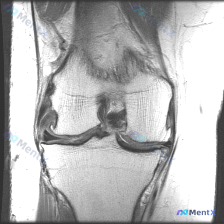

病例读片分享:膝关节MRI软骨异常的矛盾结果 刚整理了一份很有意思的读片病例,原提问说这张影像存在软骨异常,但我们完整分析完,结果和提问的判断矛盾,给大家分享一下整个过程。 影像基本信息 这是一张膝关节MRI冠状位影像,考虑是质子密度加权(PDWI)序列,这类序列分辨率高,非常适合观察膝关节的半月板...

刚整理了一个有意思的读片病例,临床和影像表现有点冲突,分享一下完整分析思路: 病例基础信息 这是一张膝关节MRI冠状位T1加权成像(T1WI),用户提示观察内容为「软骨异常」。 影像读片结果 先给大家说清楚各个结构的观察情况: 1. 骨骼结构:股骨远端、胫骨近端显示清晰,骨皮质低信号、骨髓腔中等信号...

看到这个病例很有代表性,整理了完整资料和分析思路分享给大家 病例与影像资料 本次评估的是单张膝关节MRI T1加权序列冠状位图像,临床提出问题:影像是否存在软骨异常? 对影像的详细评估结果如下: 1. 骨骼系统:股骨远端、胫骨近端骨皮质连续,无骨折,骨髓信号正常,无局灶低信号,无骨质破坏、囊变或骨赘...